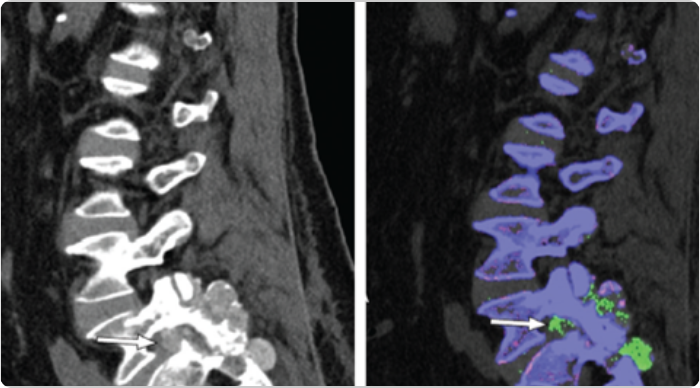

DECT scans of lower spine showing tophaceous deposits

Sagittal DECT and 3-dimensional DECT reconstruction show extensive tophaceous deposits (in green) in L1/2, L2/3, L3/4, and L4/5 lumbar discs, and also L2-L3 and L4-L5 facet joints.2

Adapted from Lu H, et al. Medicine (Baltimore). 2017;96:e7670.

KRYSTEXXA has not been studied to reverse damage to the spine or any of the body's organs.

DECT, dual-energy computed tomography.

DECT scans of lumbar spine showing tophaceous deposits

Sagittal mixed 120-kVp equivalent images of lumbar spine obtained with dual-energy CT demonstrate an intermediate-attenuation mass in the L5-S1 facet joint with bony erosions and narrowing of the neural foramen (arrow, left). Dual-energy material labeling color map overlay shows monosodium urate (green) and bone (blue and pink). Note the monosodium urate crystals crowding the left neural foramen (arrow, right).3

Adapted from Gibney B, et al. Radiology. 2020;296:276.

CT, computed tomography.